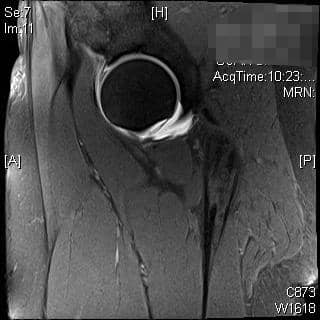

रोगी एक 39 वर्षीय महिला है जिसमें महत्वपूर्ण दाहिने कूल्हे का दर्द है जो गैर-प्रभाव लोडिंग व्यायाम, गतिविधि संशोधन और स्टेरॉयड इंजेक्शन के साथ रूढ़िवादी उपचार के बावजूद बना रहता है। वह गहरी कुर्सियों से बाहर निकलने और धुरी गतिविधियों से सबसे ज्यादा परेशान है। उनका एमआरआई किया गया था, जिसमें लैब्रल टियर दिख रहा था।

एमआरआई और सीटी का उपयोग एसिटाबुलम और समीपस्थ फीमर के आगे के मूल्यांकन के लिए किया जा सकता है। ये अध्ययन एसिटेबुलर संस्करण और नरम ऊतक के प्रभाव का बेहतर मूल्यांकन प्रदान कर सकते हैं या प्रीऑपरेटिव प्लानिंग में मदद कर सकते हैं। एमआर आर्थ्रोग्राम ऊरु गर्दन के कैम घाव के निदान में भी सहायता कर सकता है, लैब्रम या उपास्थि का आकलन कर सकता है। रेडियल अनुक्रमण सबसे अच्छा है, एक असामान्य लैब्रम कुंद दिखाई देगा या इसके आधार पर बढ़े हुए संकेत के साथ दिखाई देगा। 3, 4 एसिटैबुलर रेट्रोवर्जन के कारण पिंसर का प्रभाव, शुरू में लैब्रल विफलता दिखाएगा, जिसके बाद एक कॉन्ट्राकूप तंत्र के परिणामस्वरूप पोस्टरोहीन एसिटेबुलर कार्टिलेज में छोटे, पतले घाव होंगे। 5 इसे क्रॉस-ओवर संकेत, पीछे की दीवार के संकेत, या रेडियोग्राफ़ पर एक नकारात्मक खट्टा कोण के साथ पुन: प्रदर्शित किया जा सकता है। एमआरआई में कुंद लैब्रम, ऊरु गर्दन पर चुंबन घाव, पीछे के एसिटेबुलर कार्टिलेज का घिसना, या एक रेट्रोवर्टेड एसिटाबुलम प्रदर्शित होगा। ऊरु गर्दन के घावों के कारण कैम का प्रभाव, उपास्थि की प्रारंभिक विफलता को दर्शाता है, जिसके बाद लैब्रल फट जाता है। पार्श्व एक्स-रे पर सिर-गर्दन ऑफसेट में कमी, ऊरु गर्दन पर अतिरिक्त हड्डी की आकृति और बढ़े हुए अल्फा-कोण का आकलन निदान में सहायता कर सकता है। एमआरआई पर लैब्रम अपने आधार पर फटने का प्रदर्शन कर सकता है, एक असामान्य ऊरु सिर-गर्दन समोच्च स्पष्ट हो सकता है, या उपास्थि प्रदूषण स्पष्ट हो सकता है। रोगी 80% मामलों में कैम और पिंसर दोनों के साथ पेश होंगे, हालांकि एक रूप आमतौर पर प्रमुख होता है। 2